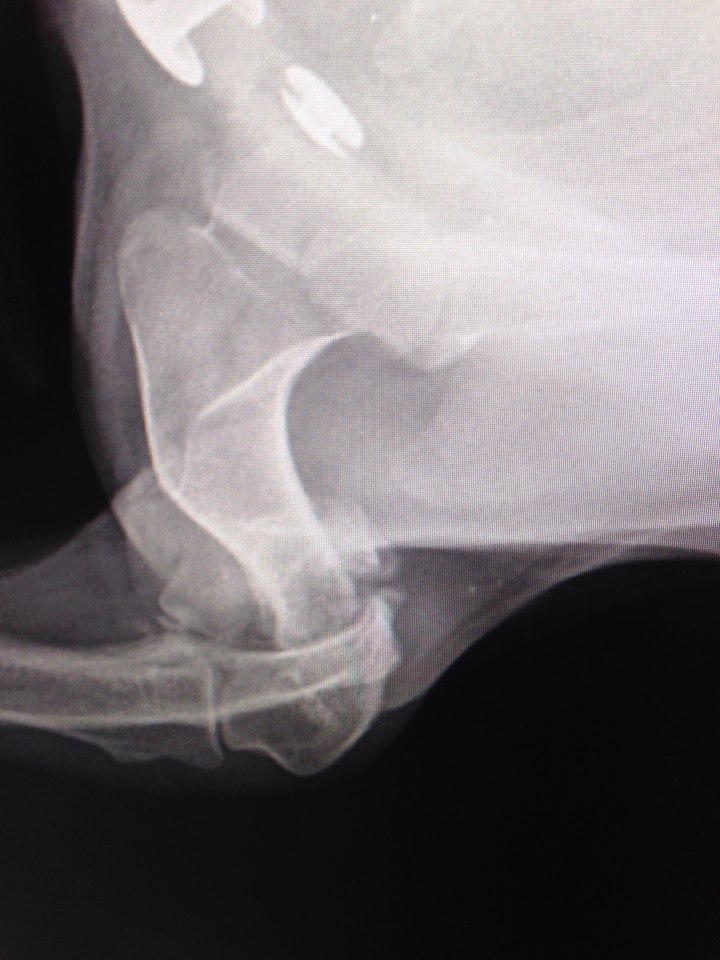

В клинику поступила с жалобами на отсутствие опоры левой грудной конечности. При осмотре обнаружилось, что у собаки нарушены анатомические контуры левого локтевого сустава и при манипуляциях с этим суставом животное испытывает боль.

Рентгенографические снимки в прямой и боковой проекциях показали, что Элли перенесла полтора-два месяца назад перелом латерального мыщелка левой плечевой кости.

Этот перелом не был должным образом пролечен. Собаке нужно было выполнить хирургическое лечение, так как такие переломы лечатся только оперативно. Все внутрисоставные переломы должны быть хирургически собраны максимально точно. Это обеспечивает полноценность работы сустава. Если нет адекватного анатомического сопоставления, будет развиваться остеоартрит, сустав придет в негодность. В данном случае собаке просто наложили гипс. За прошедшее время поверхности срослись в том виде, в каком были при переломе. Сустав полностью был разрушен.